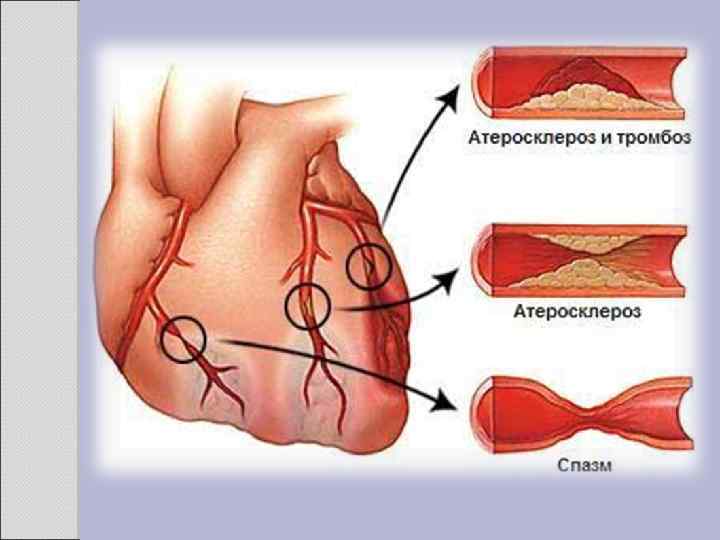

2. 1 АТЕРОСКЛЕРОЗ Атеросклероз — хроническое заболевание эластического и мышечно-эластического типа, возникающее вследствие нарушения липидного обмена и сопровождающееся отложением холестерина и некоторых фракций липопротеидов в интиме сосудов. Отложения формируются в виде атероматозных бляшек. Последующее разрастание в них соединительной ткани (склероз), и кальциноз стенки сосуда приводят к деформации и сужению просвета вплоть до облитерации (закупорки). Этиология На данный момент единой теории возникновения данного заболевания нет. Выдвигаются следующие варианты, а также их сочетания: • теория липопротеидной инфильтрации — первично накопление липопротеидов в сосудистой стенке, • теория дисфункции эндотелия — первично нарушение защитных свойств эндотелия и его медиаторов, • аутоиммунная — первично нарушение функции макрофагов и лейкоцитов, инфильтрация ими сосудистой стенки, • моноклональная — первично возникновение патологического клона гладкомышечных клеток, • вирусная — первично вирусное повреждение эндотелия (герпес, цитомегаловирус и др. ), • перекисная — первично нарушение антиоксидантной системы, • генетическая — первичен наследственный дефект сосудистой стенки, • хламидиозная — первичное поражение сосудистой стенки хламидиями, в основном, Chlamydiapneumoniae. • гормональная — возрастное повышение уровня гонадотропных и адренокортикотропных гормонов приводит к повышенному синтезу строительного материала для гормонов-холестерина.

Клиника Клинические проявления часто не соответствуют морфологии. При патологоанатомическом вскрытии обширное и выраженное атеросклеротическое поражение сосудов может оказаться находкой. И наоборот, клиника ишемии органа может появляться при умеренной облитерации просвета сосуда. Характерно преимущественное поражение определенных артериальных бассейнов. От этого зависит и клиническая картина заболевания. Поражение коронарных артерий постепенно приводит к коронарной недостаточности, проявляющейся ишемической болезнью сердца. Заинтересованность церебральных артерий вызывает либо преходящую ишемию мозга либо инсульты. Поражение артерий конечностей — причина перемежающейся хромоты и сухой гангрены. Атеросклероз брыжеечных артерий ведет к ишемии и инфаркту кишечника (мезентериальный тромбоз). Также возможно поражение почечных артерий с формированием почки Голдблатта. Даже в пределах отдельных артериальных бассейнов характерны очаговые поражения — с вовлечением типичных участков и сохранностью соседних. Так, в сосудах сердца окклюзия наиболее часто возникает в проксимальном отделе передней межжелудочковой ветви левой коронарной артерии. Другая типичная локализация — проксимальный отдел почечной артерии и бифуркация сонной артерии. Некоторые артерии, например внутренняя грудная, поражаются редко, несмотря на близость к коронарным артериям и по расположению, и по строению. Атеросклеретические бляшки часто возникают в бифуркации артерий — там, где кровоток неравномерен; иными словами, в расположении бляшек играет роль локальная гемодинамика (см. патогенез).

Диагностика заболеваний связанных с атеросклерозом включает: • опрос больного и выяснение симптомов болезни: симптомы ишемической болезни сердца, симптомы нарушения мозгового кровообращения, перемежающаяся хромота, симптомы брюшной жабы и пр. ; • общий осмотр больного: признаки старения организма, выслушивание систолического шума в очаге аорты; • обязательно пальпация всех артерий, доступных к пальпации: аорта, наружные подвздошные артерии, общие бедренные артерии, подколенные артерии, артерии тыла стопы и задней большеберцовой артерии, лучевой и локтевой артерий, сонных артерий; • определение систолического шума над аускультативными точками артерий; • при подозрении на поражение артериального русла нижних конечностей - определение капиллярного ответа; • определение концентрации холестерина в крови и определение липидного баланса крови; • рентгенологическое исследование органов грудной клетки, рентгенэндоваскулярные методы обследования; • ультразвуковое исследование сердца и органов брюшной полости и забрюшинного пространства; • доплерография сосудов конечностей, а лучше ультразвуковое дуплексное и триплексное сканирование артерий брахиоцефального отдела, артерий нижних конечностей, аортоподвздошного сегмента, а также транскраниальныйдоплер.